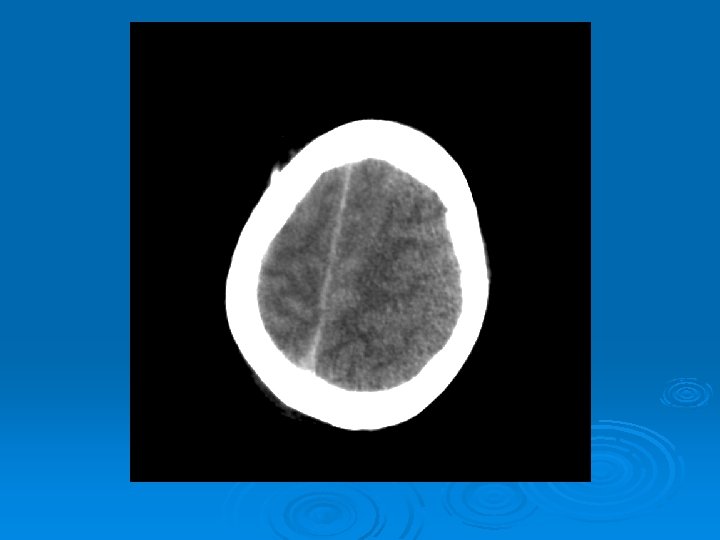

Course: Ø 3 PM, RN noticed anisocoria and L pupil non-reactive. Ø Neurology STAT dose mannitol and w/ dilantin. Ø Pt went for stat head Ct:

CT head 2/11/07 Ø A right frontal ventriculostomy catheter Ø Diffuse sulcal effacement with thickening of the cortex. Ø Loss of gray-white differentiation and hypodensity in the left parietooccipital region. Ø There is diffuse hypodensity of the cerebellum and brainstem. Ø Ø Ø The basilar cisterns are nearly completely effaced. Ø Impression: Ø Worsened diffuse cerebral edema The lateral ventricles are smaller

Course: Ø Neurosurgery saw pt: on exam she had lost cough, gag reflexes, corneal reflexes, she had flexed RUE, semipurposeful with bilateral extended LE. Ø Concern for herniation: placed Ø ICP 35 -40 10 th-11 th EVD